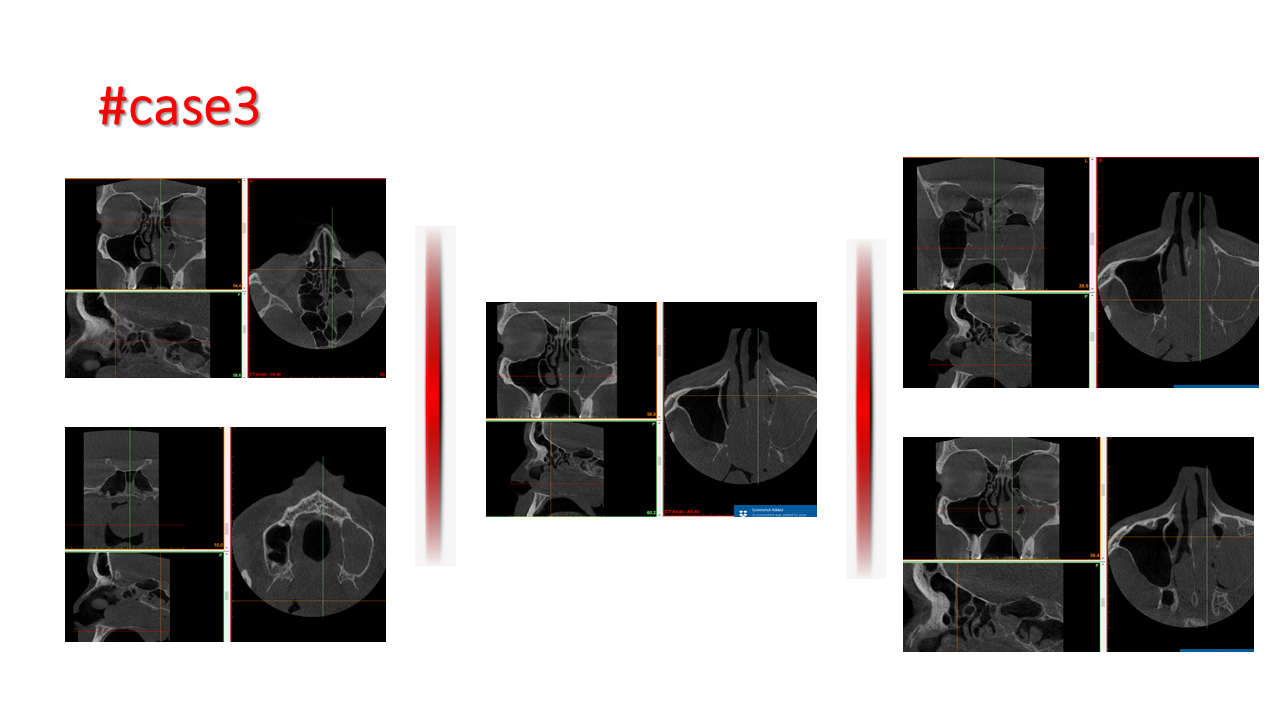

FESS Case Review and Radiologic Analysis (30.09.2016)

Case-based presentation focused on pre- and postoperative imaging in functional endoscopic sinus surgery (FESS). Includes anatomical landmarks, surgical variations, sinus pathology, and technique evaluation. Delivered by Dr. Levon Galstyan at AAOMFS.